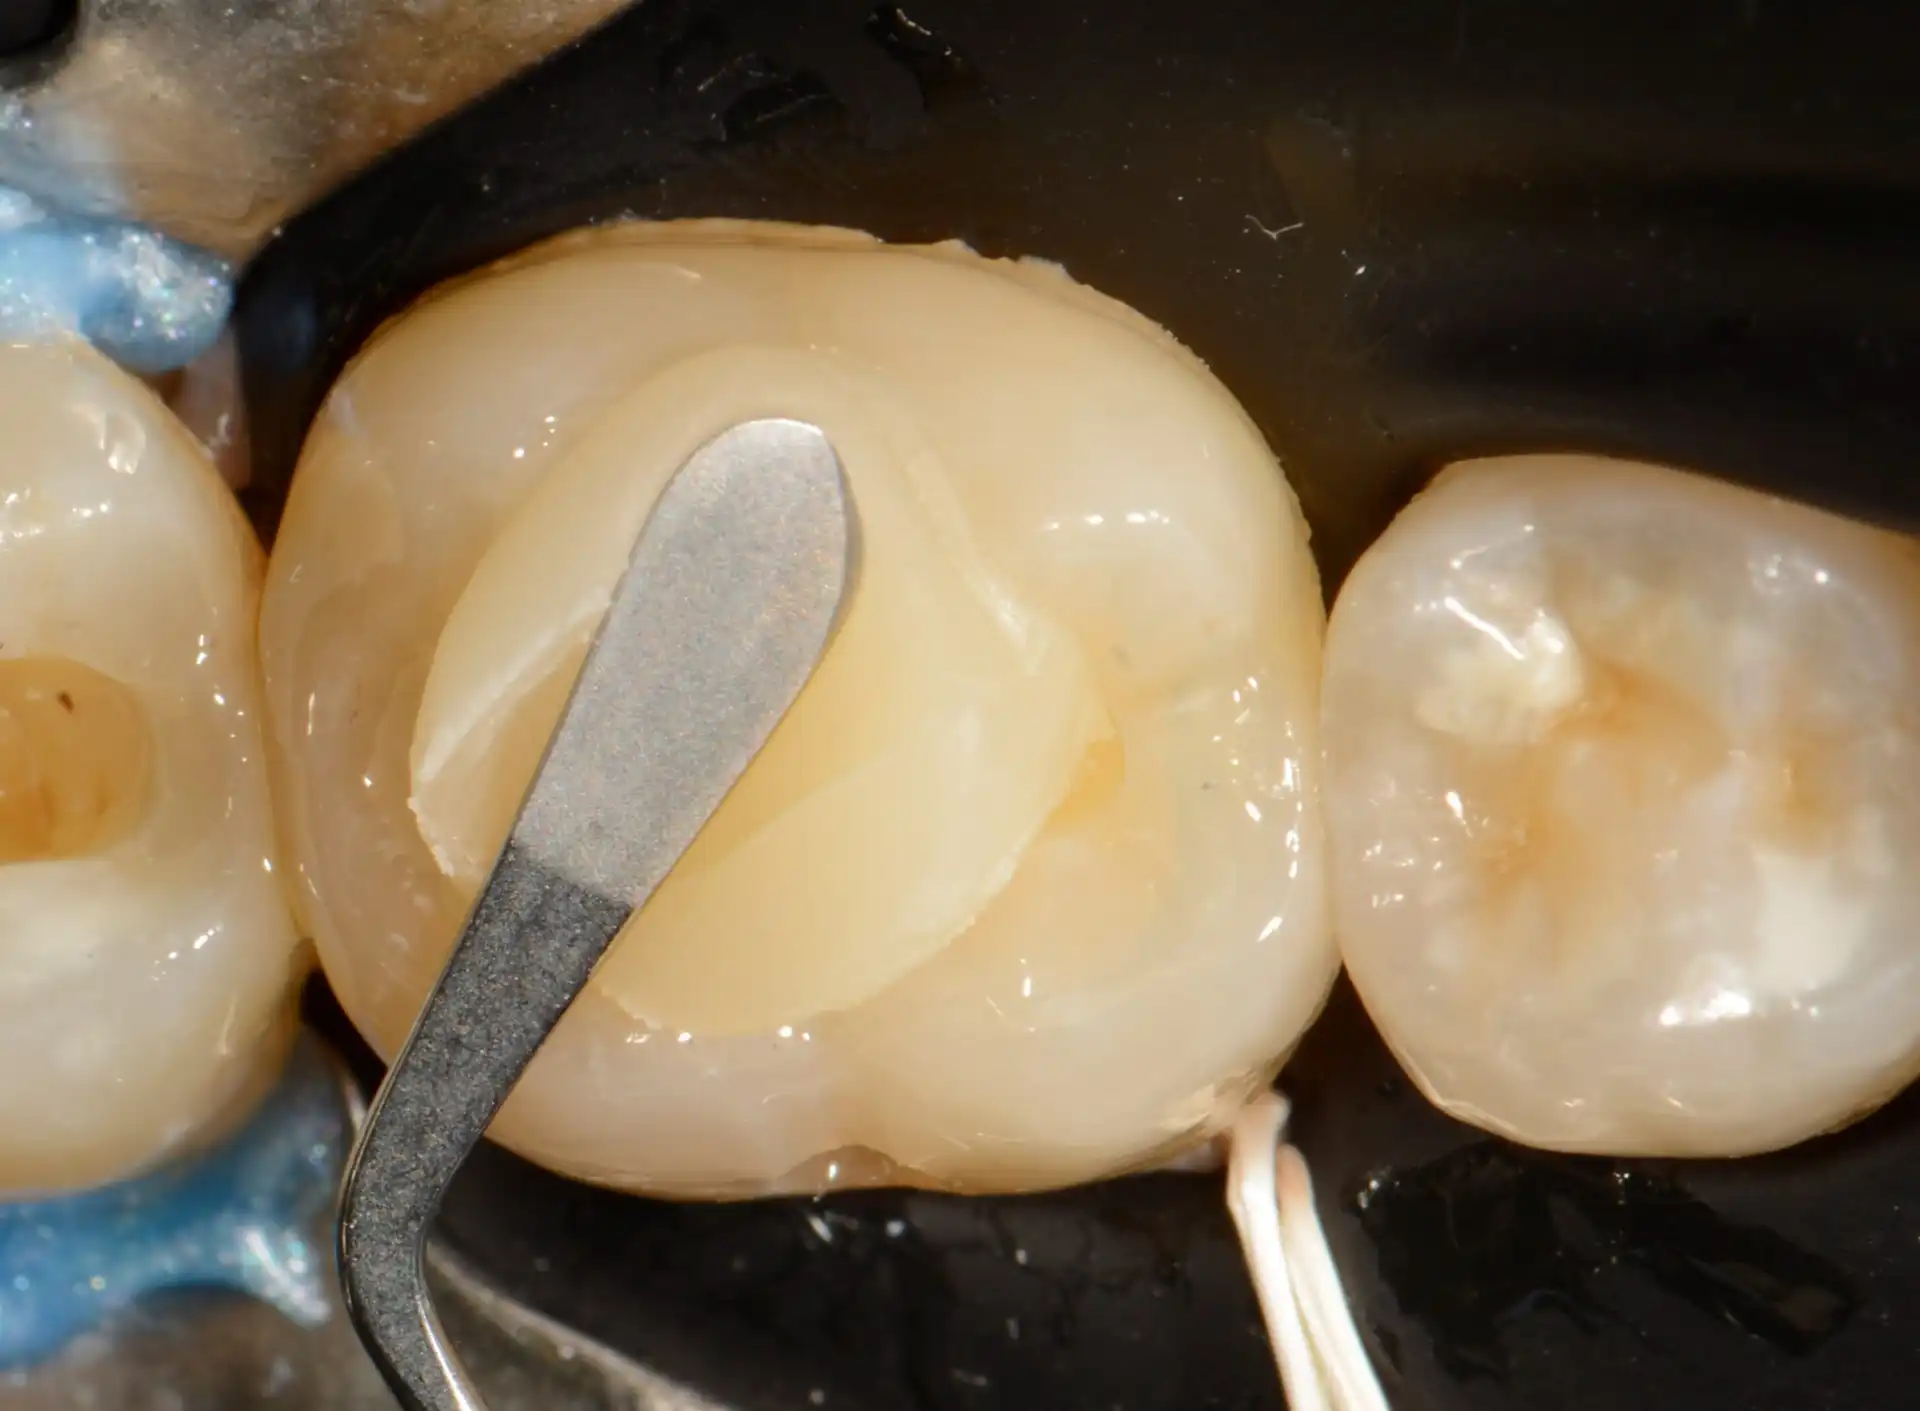

Confira este caso clínico de restauração dentária posterior, terceiro molar, com a resina tipo Bulk da 3M.